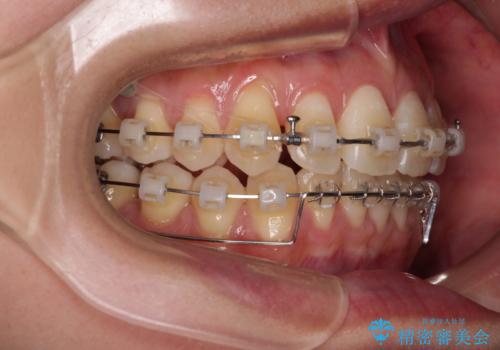

- クリアブラケット

- 1年6ヶ月

- 上顎前歯の突出感を気にして来院された患者様です。

舌の突出癖の影響で、歯列が前方に飛び出いた形態となっている状態でした。

抜歯矯正とするような歯列ではないため、舌のトレーニングを行いながら歯列を側方に拡大させることで口元の突出感を改善することとしました。